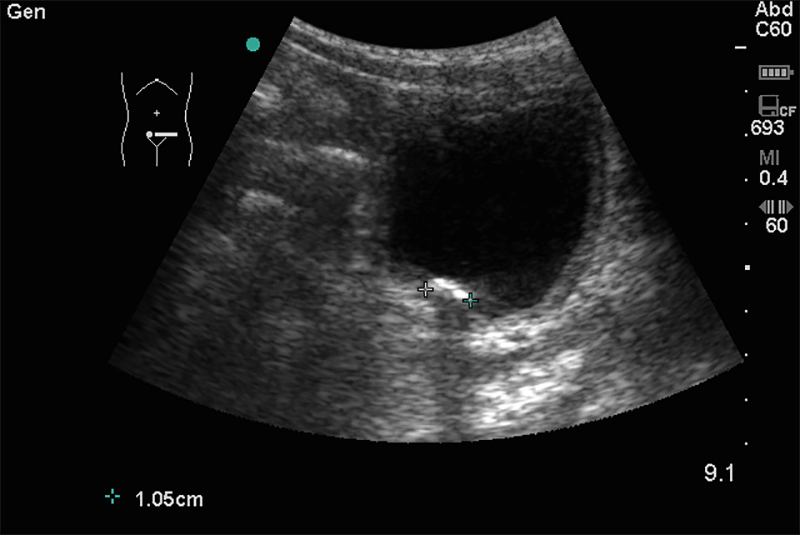

A máj, epe, epeutak, hasnyálmirigy, vesék és lép alakja, szerkezete tisztázható. Felvilágosítást ad a hasi nagyerek, a gyomor- és bélfalak állapotáról. A hasban előforduló egyéb esetleges kóros folyamatok (kóros folyadékgyülemek, daganatok, nyirokcsomók) ábrázolhatóak.

Hasi fájdalmak, derékfájdalom, egyéb hasi panasz (puffadás, teltségérzet, emésztési és székelési problémák) fennállása esetén első vizsgálatként ajánlott.